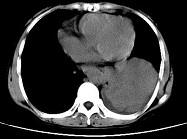

问题 女,55岁,胸痛伴咯血丝痰1周,胸部CT如图,最可能的诊断为 ( )

选项 A.转移性肺癌 B.左侧周围型肺癌并肺内转移 C.左侧中央型肺癌并肺内转移 D.多发性肺脓肿 E.结节病

答案 B